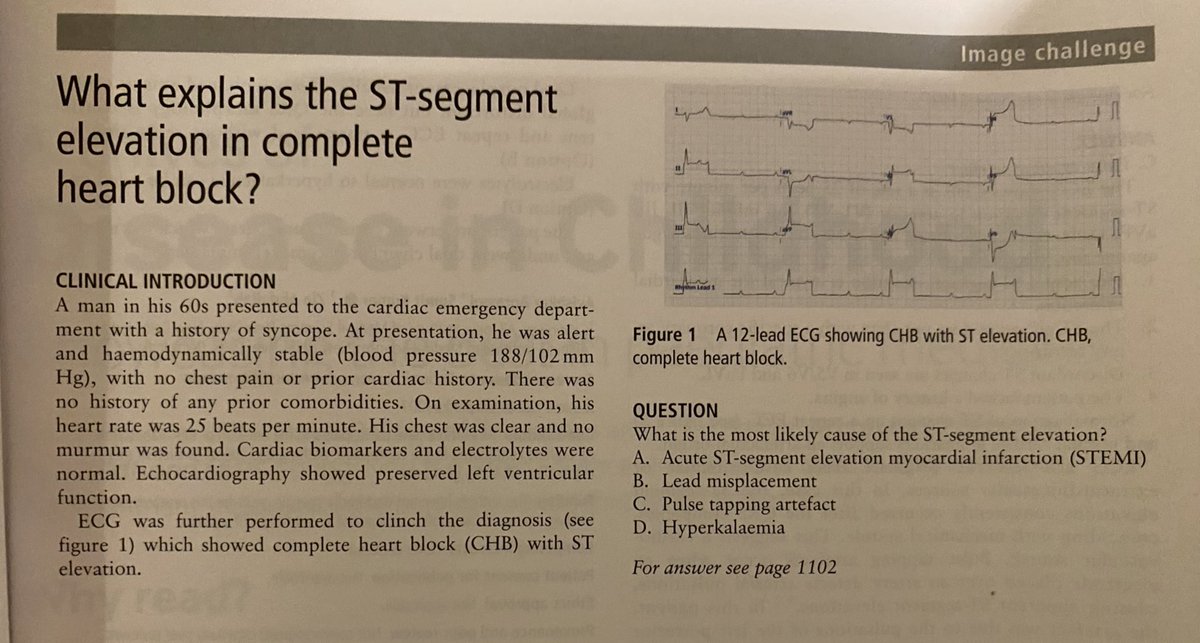

Amazing. Just written an ECG textbook (out very soon) and yet I’d NEVER come across this before. Still learning! Nice work @Heart_BMJ @sumitku3007 #CardioEd #CardioX #cardiology #EPeeps

Amazing. Just written an ECG textbook (out very soon) and yet I’d NEVER come across this before. Still learning! Nice work @Heart_BMJ @sumitku3007 #CardioEd #CardioX #cardiology #EPeeps